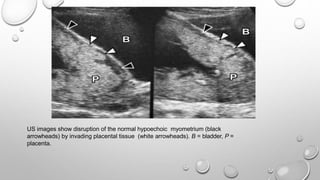

US images show disruption of the normal hypoechoic myometrium (black

arrowheads) by invading placental tissue (white arrowheads). B = bladder, P =

placenta.